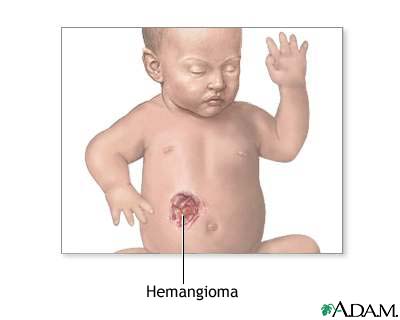

A hemangioma is an abnormal buildup of blood vessels in the skin or internal organs.

The hemangioma may be:

- In the top skin layers (capillary hemangioma)

- Deeper in the skin (cavernous hemangioma)

- A mixture of both layers of skin

Symptoms of a hemangioma are:

- A red to reddish-purple, raised growth on the skin

- A massive, raised, bluish lump with visible blood vessels

Most hemangiomas are on the head, neck, or extremities.